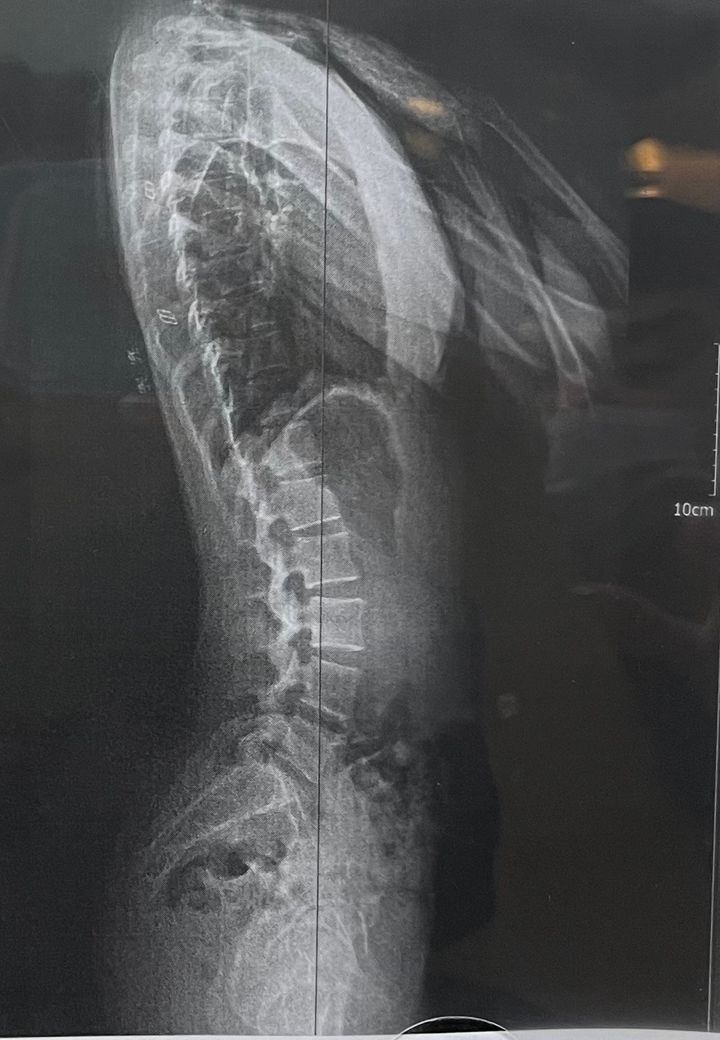

제가 목 통증으로 병원가서 엑스레이를 찍었다가 도수치료를 받게되었는데 물리치료사분이 저보고 후반경사라고 하더라구요 근데 저는 제가 전반경사라고 확신하고 살았어서 잘못 말하신줄 알았는데 아니래요.. 제가 허리도 커브가 심하고 오리궁둥이에 벽에대고 서도 사이가 붕뜨고 아랫배도 나와있거든요 전형적인 전방경사 특징아닌가요? 치료사분은 후반경사로 인한 커브라는데 인터넷 전반경사 사진들이 딱 제모습이거든요 엑스레이는 제껀데 봐주시고 답변 부탁드려요

• 1번 째 사진

엑스레이상으로 볼때에는 골반의 전방경사로 보입니다 전방경사의경우 허리커브가 더 심해질수있고 오리궁댕이가 가장큰특징입니다~

엑스레이 사진상으로는 전방경사인 것으로 확인 됩니다. 전방 경사인 경우 오리엉덩이가 특징이며 장요근의 긴장 및 둔근의 약화로 인해서 발생 할 수 있고 허리의 커브가 증가되는것이 특징입니다.

제가 보기에는 전방경사가 맞는것으로 보여집니다

전방경사로 보입니다 전방경사는 골반이 앞으로 넘어지듯 쏠린 변형으로 오리궁뎅이가 대표적 특징이가 장요근 긴장,둔근약화로 인하여 변형될 수 있습니다 후방경사 운동을 꾸준히 해주시길 바랍니다

희미해서 잘 보이지가 않네요. 문제가 될 정도로 후방경사, 전방경사는 아닌것으로 보입니다. 조금만 신경쓰시면 정상적인 골반의 경사가 나타날것으로 보이는데, 사진상으로는 약간의 과전만이 있기는 하네요. 과전만이 무조건 전방경사를 의미하지는 않습니다. 그리고 엑스레이는 조금씩 바뀌기 때문에 다음번에는 전방경사로 나올 수도 있습니다.

말씀하신 것들은 골반 전망 경사의 특징이 맞습다. 사진상에서도 천골이 앞쪽으로 누워 있는 것이 관찰되며 골반 전체적으로 앞쪽으로 기울어져 있는 것으로 보입니다. 적절한 운동과 체형교정 및 체중 조절이 필요해 보입니다.